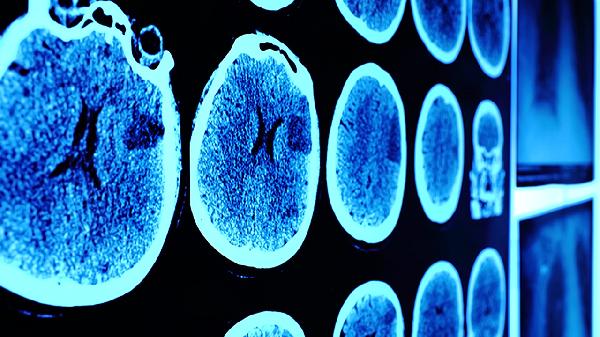

伤后3天、1周、1个月需神经外科随访,通过格拉斯哥昏迷量表评估恢复情况。学生及运动员需经医生评估后逐步恢复学习训练。复查时应携带首次就诊的影像资料,便于对比观察。老年患者或既往有脑血管病史者需增加复查频率。